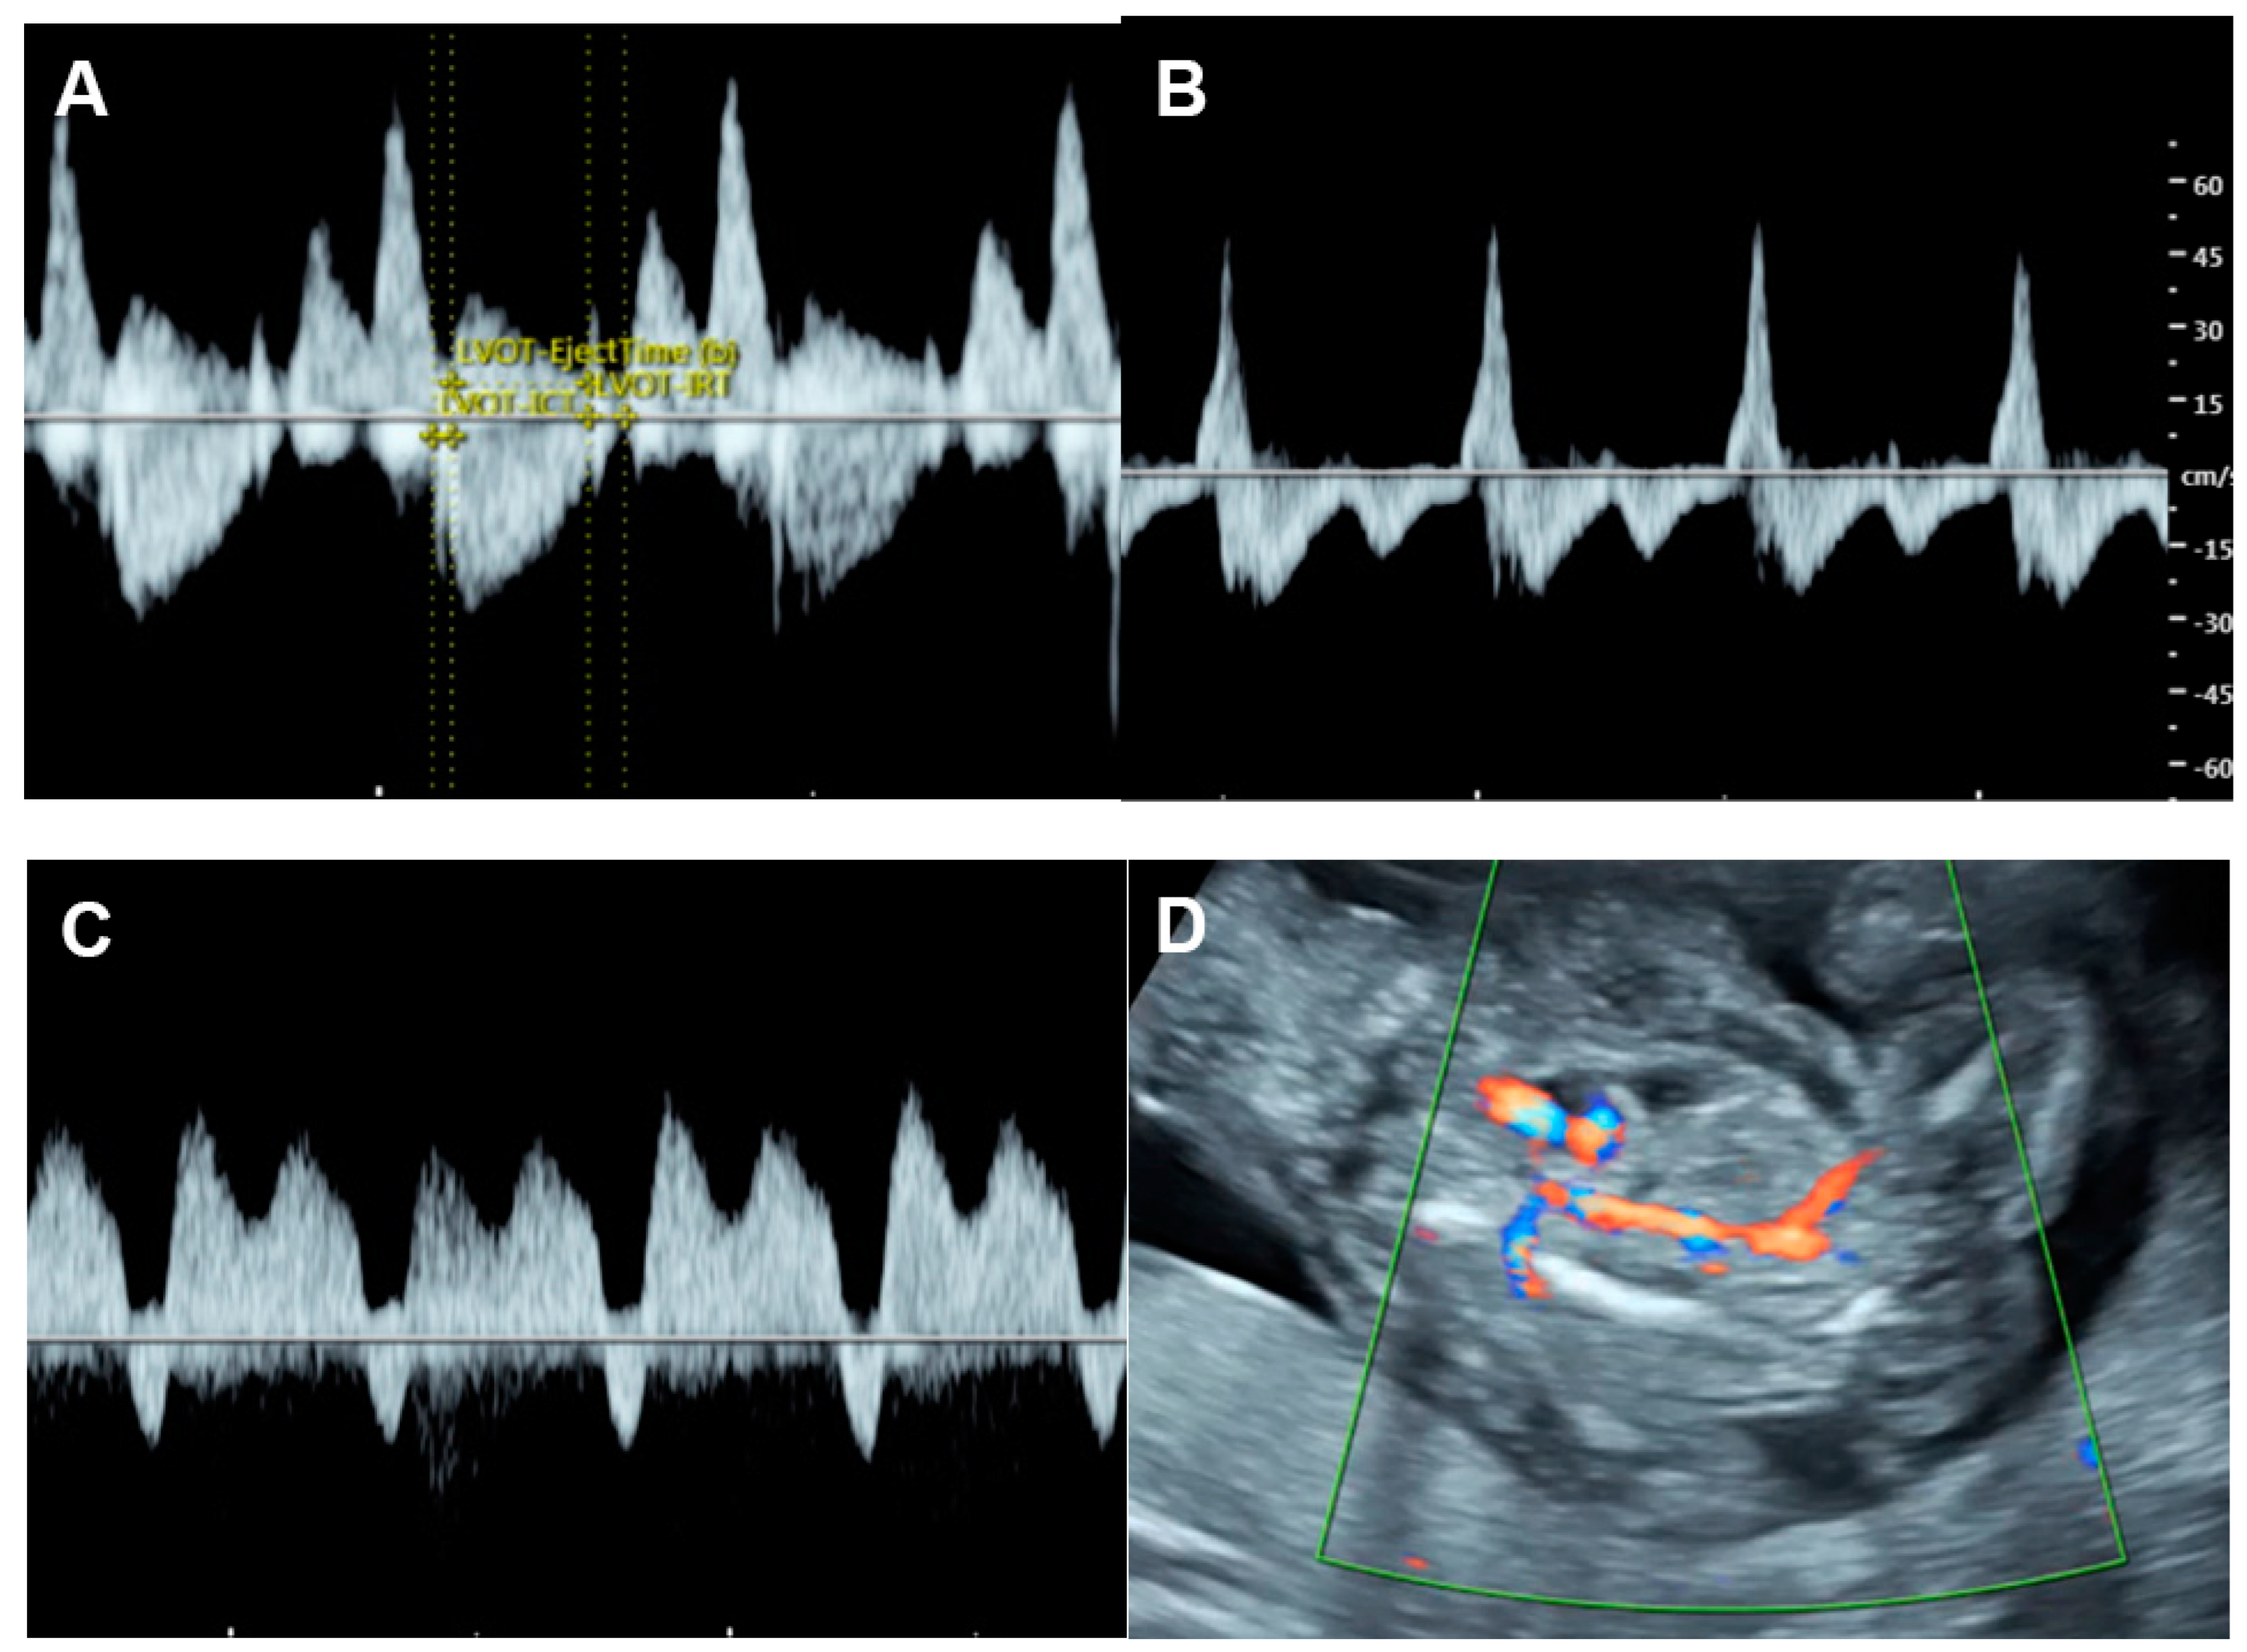

5.6. Critical Aortic Stenosis

- Tulzer, G.; Gudmundsson, S.; Sharkey, A.M.; Wood, D.C.; Cohen, A.W.; Huhta, J.C. Doppler echocardiography of fetal ductus arteriosus constriction versus increased right ventricular output. J. Am. Coll. Cardiol. 1991, 18, 532–536. [Google Scholar] [CrossRef]

- Mori, Y.; Rice, M.J.; McDonald, R.W.; Reller, M.D.; Wanitkun, S.; Harada, K.; Sahn, D.J. Evaluation of systolic and diastolic ventricular performance of the right ventricle in fetuses with ductal constriction using the Doppler Tei index. Am. J. Cardiol. 2001, 88, 1173–1178. [Google Scholar] [CrossRef]

- Wen, J.; Guo, X.; Cai, S.; Xu, D.; Zhang, G.; Bai, X. Fetal Ductus Arteriosus Premature Constriction. Int. Heart J. 2022, 63, 722–728. [Google Scholar] [CrossRef]